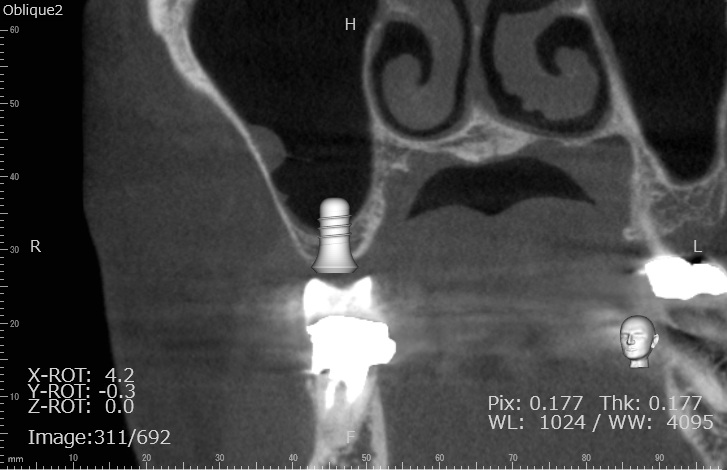

| 治療名 | GBRとインプラントを行った症例 |

| 治療説明 | インプラントを埋入予定の部位において、骨の吸収が見られたため、インプラント埋入と同時に小規模な骨造成(GBR)を行いました。治癒期間を経て、最終的にセラミックの上部構造を装着し、自然な見た目としっかりとした噛み合わせを回復しました。 |

| 治療回数・期間 | 6ヶ月 |

| 副作用とリスク | インプラント治療は、入れ歯やブリッジに比べて治療期間が長くなる傾向があります。骨造成が必要な場合は、さらに治療期間が延びることがあります。 また、手術後には一時的な違和感や痛み、腫れ、出血などが生じる場合がありますが、通常は2日〜1週間ほどで落ち着きます。 |

| 料金(税込) | GBR〈小規模骨造成〉:110,000円 インプラント一次手術:220,000円 二次手術:55,000円 上部構造〈セラミック〉:165,000円 合計:550,000円 |